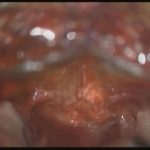

術中写真

摘出 後